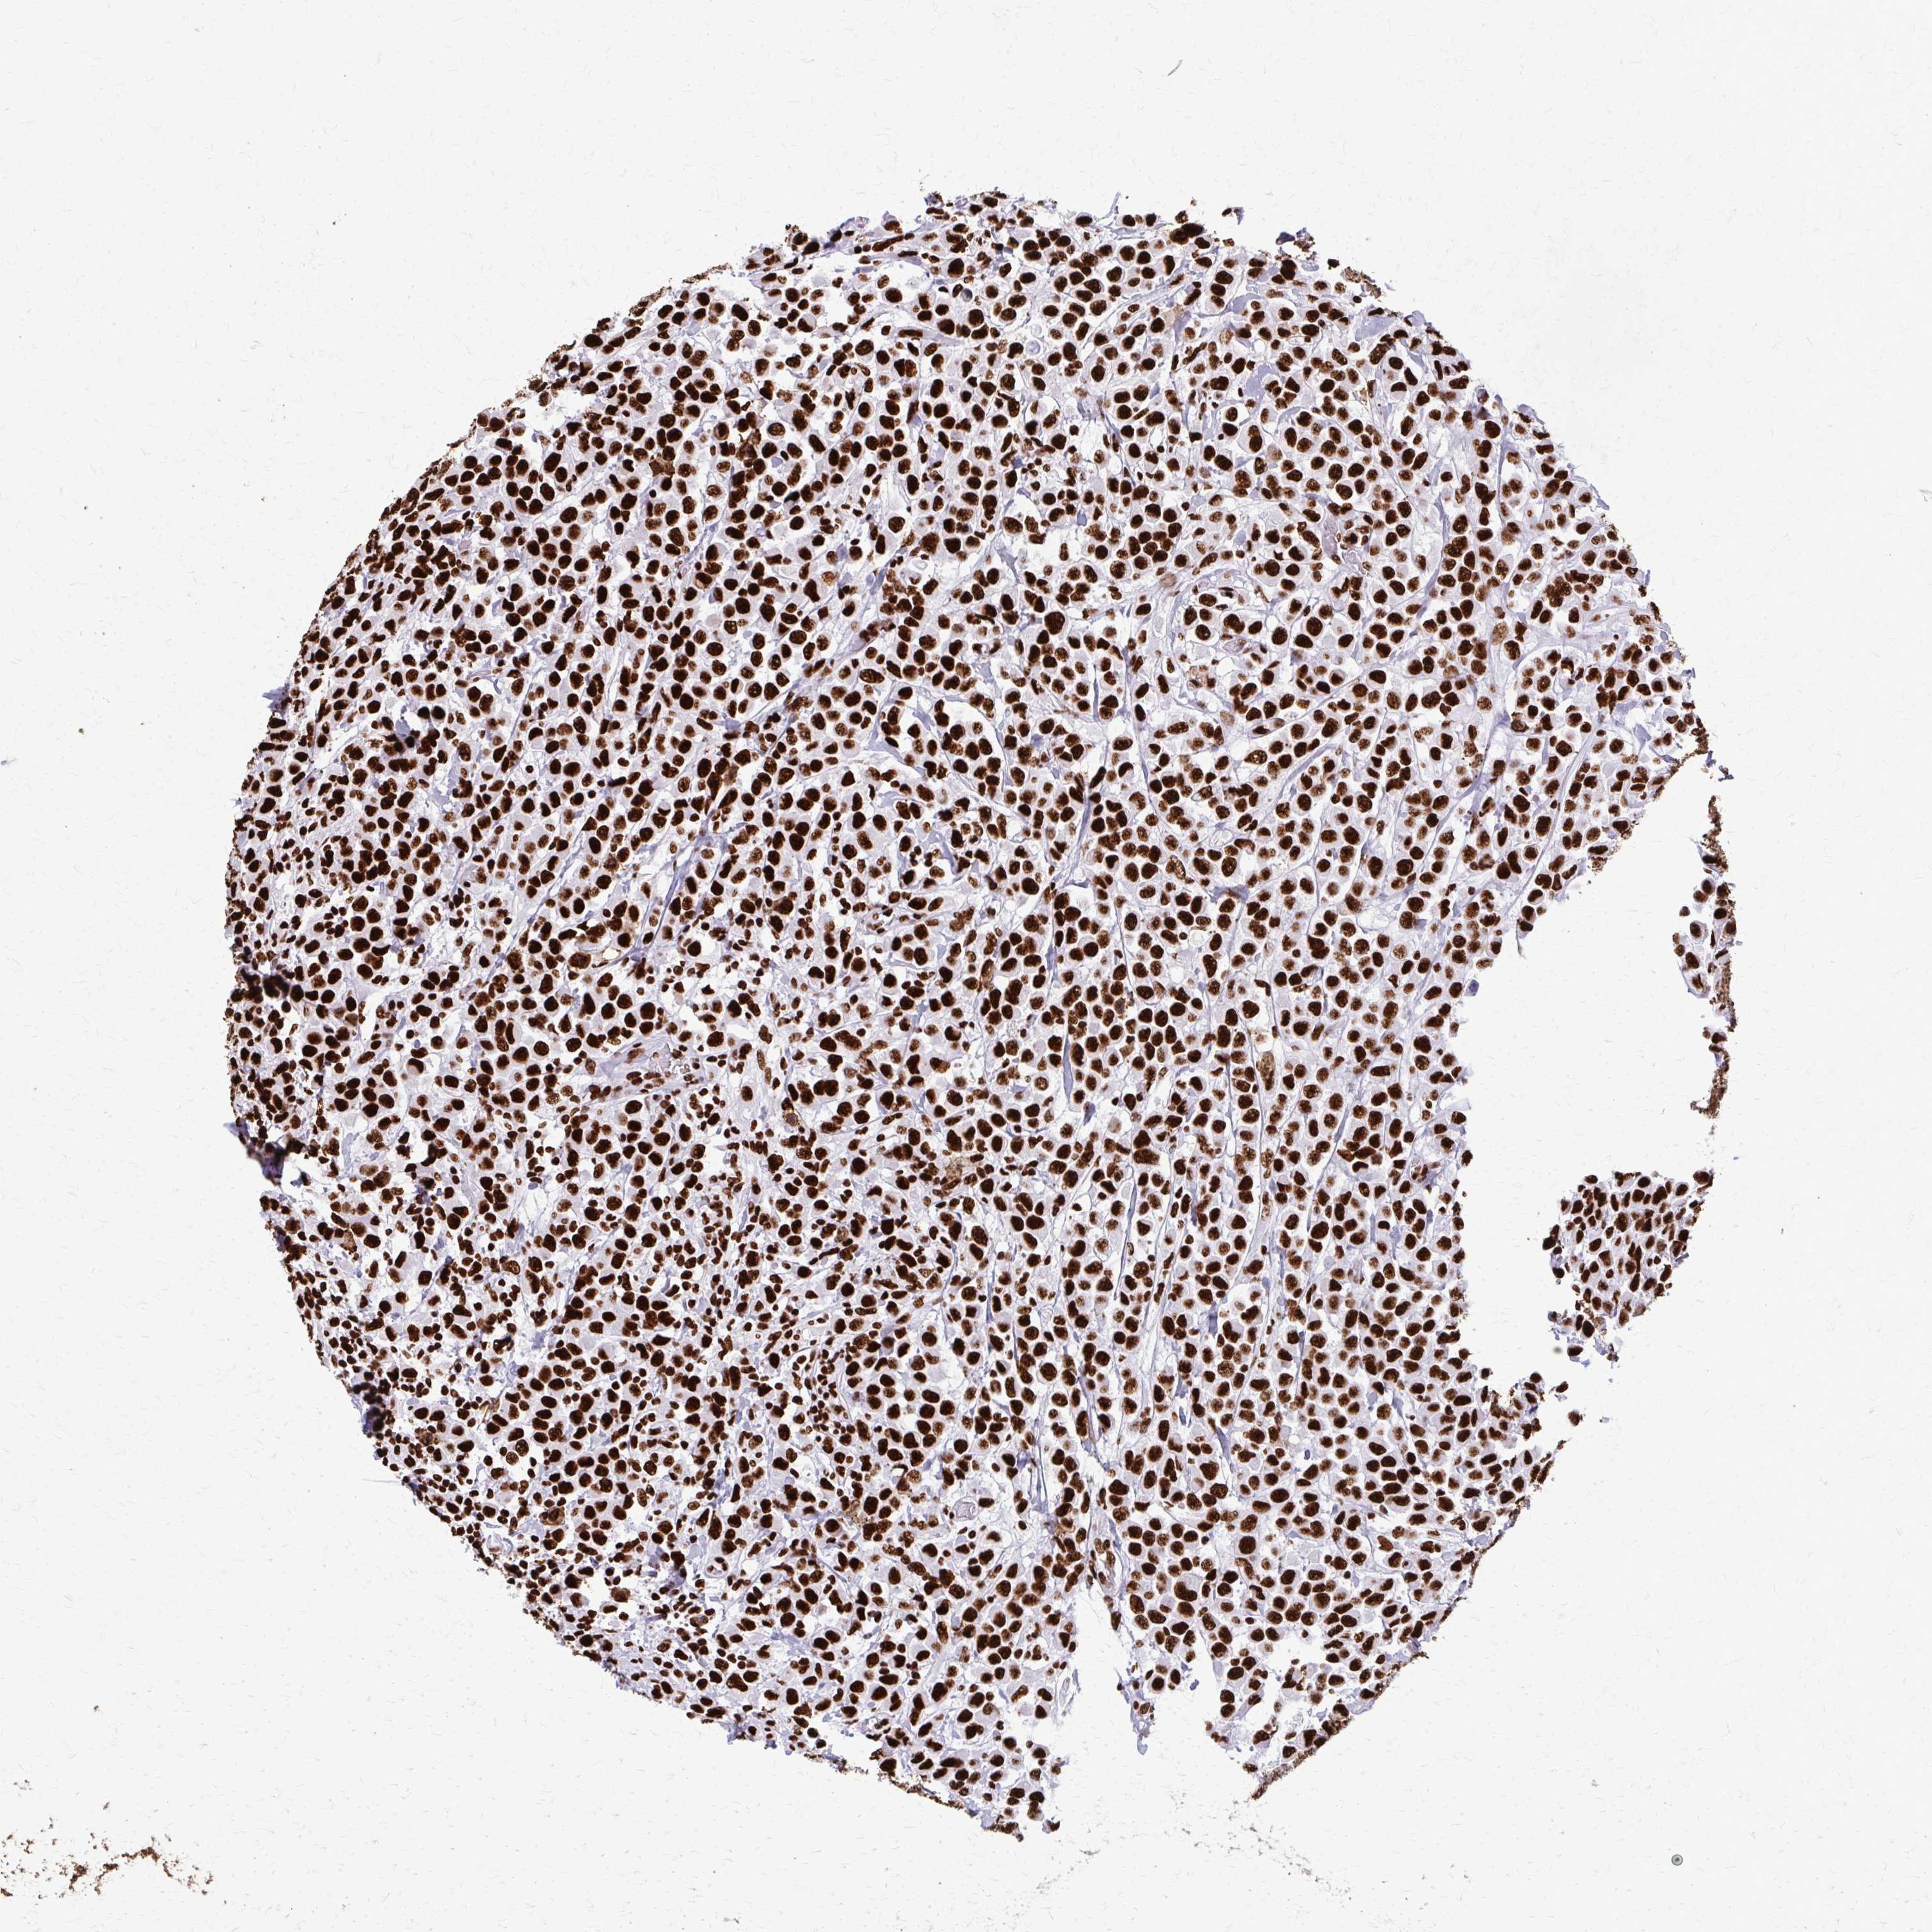

BRCA TCGA BRCA VALIDATION PROTEIN EXPRESSION

ANTIBODIES

AND

VALIDATION